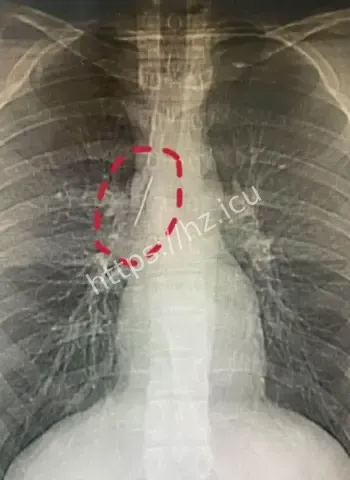

哎呦喂这事儿听起来就跟天方夜谭一样,一个安徽的17岁小伙子平时活蹦乱跳的,准备去参军体检,结果医生一照X光片子,眼睛直接瞪圆了,胸腔里居然稳稳当当藏着一根5厘米长的缝衣针。这针估计从小时候就钻进去了,整整17年啊,小伙子吃饭睡觉打球跑步啥都没耽误,身体愣是没闹过一点别扭。换成别人早疼得满地打滚了,他倒好,像没事人似的,这运气简直逆天到让人羡慕嫉妒恨。 想想这17年里,针就这么安静待着,没移位没发炎没刺着要害,估计是身体自动给它裹了一层保护膜,把它当成了自家摆设。

最离谱的是,这针很可能他1岁那会儿不小心扎进去的。小宝宝那时候到处乱爬乱抓,说不定妈妈正缝衣服,他一扑腾就中招了,结果针就这么悄无声息地进了胸腔。17年过去,他从奶娃娃长成大小伙,针却一直老老实实待着,没引起任何不舒服。平时感冒发烧都没多想过胸口,这适应力也太强了吧。 从道理上讲,小孩子身体正长着,组织慢慢把针包得严严实实,像给它建了个小房子隔离起来。没碰着肺叶心脏血管,纯靠运气加体质,简直是活生生的人体奇迹。

参军体检本来是查身体合不合格,谁知道成了挖宝现场。X光一扫,医生估计当时就傻眼了,这么大一根针亮闪闪地躺在胸腔里,小伙子自己都蒙圈了,心想我这身体里藏了啥秘密武器啊。幸好发现及时,要不然以后训练强度一大,万一针跑偏了,后果真不敢想。 这事儿也给大伙提了个醒,重要关口体检千万别马虎,尤其是参军这种人生大事,啥隐藏问题都能揪出来。小伙子估计现在又惊又喜,喜的是没出大事,惊的是自己居然带了17年“隐形伴侣”。

深入扒一扒,这针为啥能跟身体和平共处这么久呢。首先位置挑得好,没扎着要害器官,胸腔空间大给它留了余地。其次人体有自我保护本能,会分泌纤维组织慢慢把它包裹住,防止感染和移位。小时候扎入,身体还在发育,适应起来更容易。再次可能没带细菌进去,运气成分占大头。 这案例搁医学上都算罕见,值得研究研究,说不定以后处理类似异物就有新办法了。不过小伙子以后肯定得做个小手术取出来,不然总是个小隐患。希望手术顺顺利利,他的参军梦还能接着追,这段经历以后说出去绝对是别人听不够的传奇。